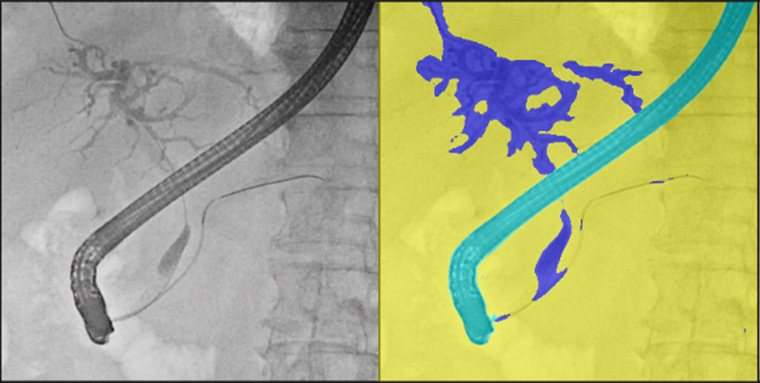

ERCP中に撮影したX線透視画像上にCT画像を用いて作成した胆管・膵管3D像を重畳表示している様子

また、今回発売する二つのモデルは、2025年4月に発売したソフトウェア「VisualAID-ERCPプランニング-」*7にも対応。本ソフトウェアは、ERCP中にCUREVISTAシリーズで撮影したX線透視画像上に3Dで作成した胆管・膵管の画像を重ねて表示することで、臓器との重なりなど解剖学的構造の把握が容易になることが期待できます。本ソフトウェアでは、これまでCT画像とMRCP画像*8で3D画像を作成する必要がありましたが、今回新たにCT画像のみで3D画像を作成できるようになりました。これにより、MRI撮影を実施しない医療機関での対象被検者の増加が見込まれます。さらに3D画像作成時にCT画像とMRCP画像の位置合わせの作業が不要となることでワークフローの向上が期待できます。当社のIT技術とX線透視装置を連携させた新しいワークフローにより、医師の診療の高度化・効率化に貢献します。

AI技術を活用して開発された造影剤強調処理により、ERCP実施時に造影された胆管領域を検出し、コントラストを強調します。本機能を使用しない透視画像よりも、胆管領域の視認性が向上します。本機能により、1検査あたりの造影剤使用量を低減し、被検者の身体的負担の軽減が期待できます。

胆管領域を検出しコントラストを強調した様子(右画像)